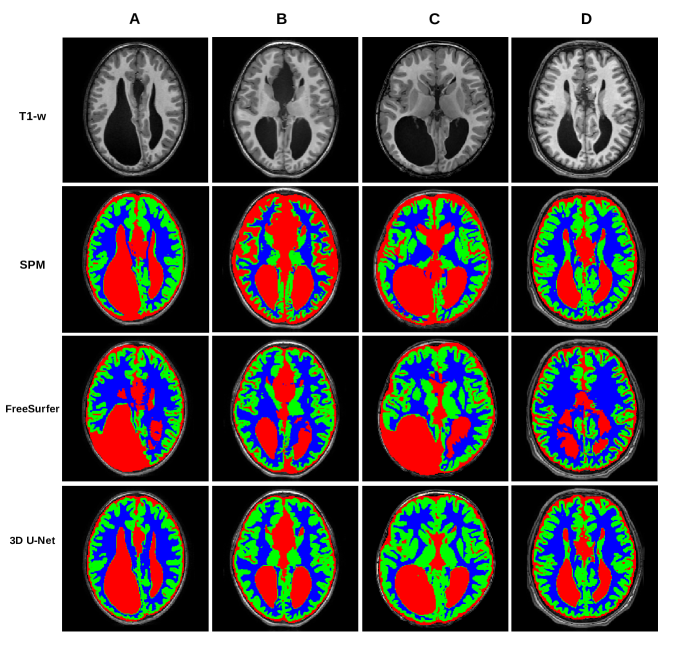

[Uncaptioned image]

This is an extension of Figure 1, i.e. paradigmatic segmentations of patients with Agenesis of Corpus Callosum, where we show SPM and FreeSurfer that we excluded in the manuscript, together with the 3D U-Net for comparison. The segmentations of SPM and FreeSurfer have major errors in the ventricles and in the area of the thalami and caudate. SPM probability maps were thresholded at p=0.4𝑝0.4p=0.4 which was the optimal choice to reduce overlap between tissues and to reduce false positives.